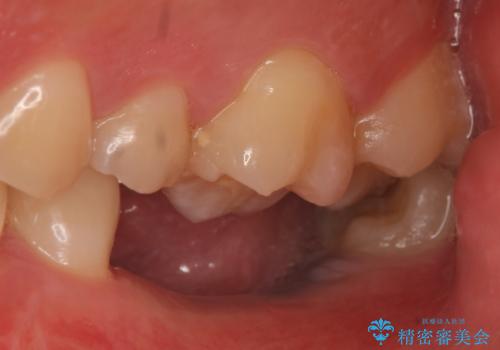

- 数年前に左下の奥歯を2本失ってから物が咬めないため何とかして欲しいと当院にいらっしゃった方の症例です。

左下にインプラント(ストローマン)を2本埋入し、オールセラミッククラウンによる補綴を行いました。

- オールセラミッククラウン…¥100,000×2、仮歯…¥10,000×2、インプラント(ストローマン)…¥200,000×2、カスタムアバット…¥100,000×2費用は治療当時の料金となります